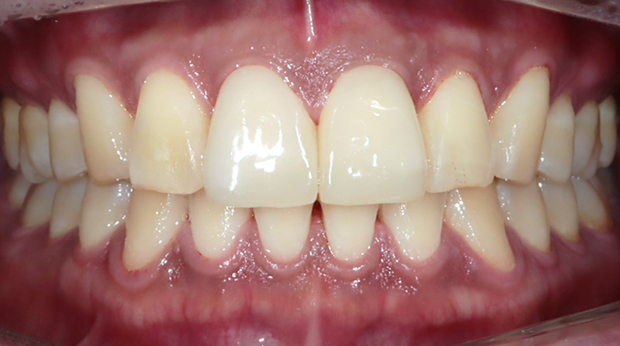

라미네이트